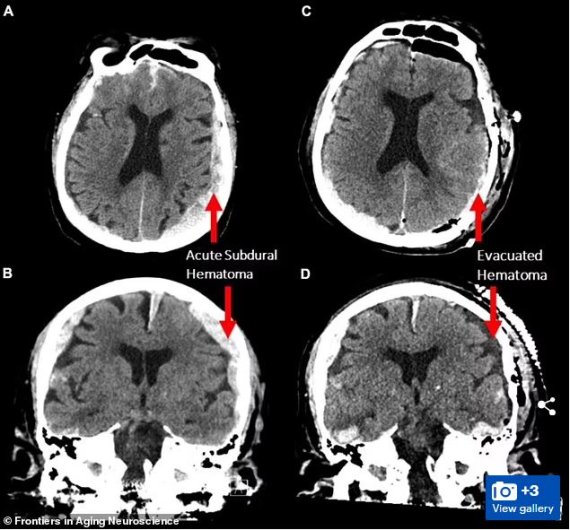

[서울=뉴시스]죽기 직전 지난 삶의 중요한 순간들이 주마등처럼 머리 속을 스쳐 지나간다는 말이 사실일 수 있음을 시사하는 과학적 증거가 우연히 포착됐다고 BBC가 23일(현지시간) 보도했다. 한 과학자 팀이 뇌전증(간질)에 걸린 87세 환자의 뇌파를 측정하던 도중 이 환자가 예상치 못하게 심장마비를 일으켜 사망하면서 그의 뇌파가 약 30초 가량 꿈을 꾸거나 기억을 떠올리는 것과 같은 패턴을 따른다는 사실이 밝혀졌다. <사진출처 : 데일리 메일> 2022.2.24

젬마 박사팀은 그러나 단 하나의 연구만으로 광범위한 결론이 도출될 수는 없다고 경고했다. 특히 환자가 뇌전증이었고, 출혈이 있고, 뇌가 부어 있었기 때문에 상황은 더욱 복잡하다. 젬마는 "단 한 가지 사례만으로 이 같은 보고를 하는 것이 결코 편하지 않다. 2016년 최초 (뇌파)촬영 이후 비슷한 사례를 찾아봤지만 성공하지 못했다"고 말했다.